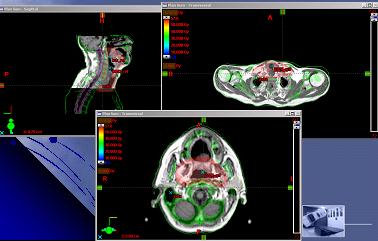

Plánování IMRT I.

Plánování IMRT II.

Optimalizace pomocí modulu Helios

- Volba počtu polí

- Stanovení horních a dolních mezí dávky a jejich priorita pro jednotlivé struktury

- Optimalizace fluence pomocí modulu Helios

- Export k výpočtu pohybu MLC a stanovení techniky (sliding window v. step and shoot)

- Použití dynamického pohybu MLC „vykreslí“ dávku tam, kde ji potřebujeme

- Výpočet dávky a MU

- V případě potřeby zpětná editace optimální fluence a opětný přepočet pohybů MLC a MU